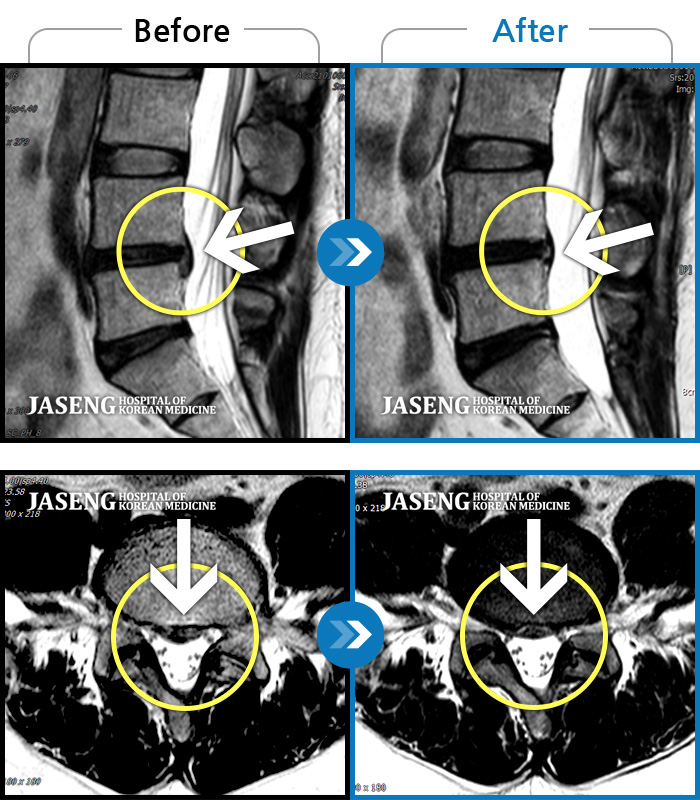

Before

After

허리통증이 심해서 숙이기 어렵고 차에서 내리기 힘들었습니다.

2021.01.06 ~ 2025.03.10